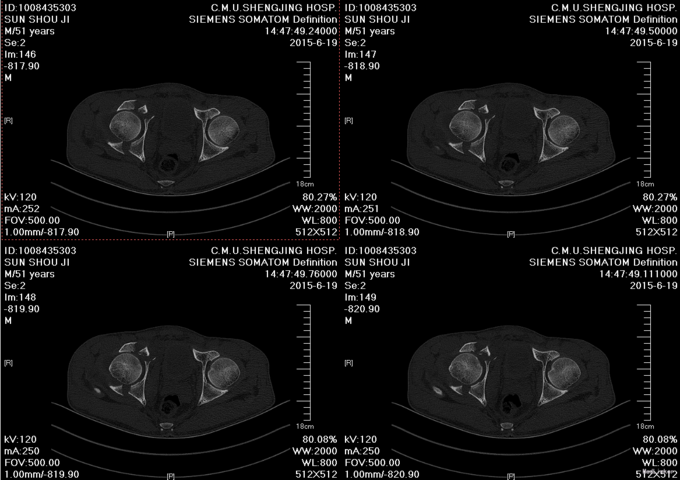

患者于2015年6月10日因车祸摔伤右侧髋关节,出现右髋部疼痛及活动受限。疼痛于活动后加重,休息可稍缓解。后就诊于营口市中心医院行骨盆三维CT示“右髋臼粉碎性骨折”,建议手术治疗,给予胫骨结节骨牵引术,患者于6月17日收入我院运动关节科病房,于6月19日转入我科。

患者入院后急诊行右髋关节脱位手法复位术,右胫骨结节骨骼牵引术。术后患者骨骼牵引约8公斤,术后约一星期后择期行右髋关节骨折切开复位钢板内固定书,术后患者病情平稳,术后三天转入当地医院继续治疗。